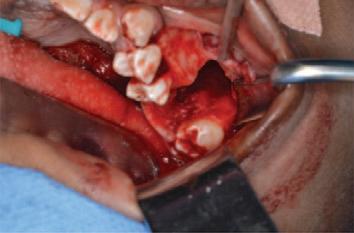

Daniel and Kayla are seven-year-old twins. They live with their parents in an estate in a large town. They are both outgoing and busy children. They enjoy school and activities with their friends. Daniel has mild autism. He has a special needs assistant in his classroom who helps him with his reading and language activities.

Daniel and Kayla have had uneventful visits to their family dentist once a year since infancy. Their teeth are brushed twice daily by their father. It is more challenging for Daniel as he does not always cope well with the flavour of the toothpaste. Recently, Daniel has found it more difficult due to sensitivity. Their dentist advised that Daniel has molar incisor hypomineralisation (MIH) and there was enamel breakdown on his newly erupted lower first permanent molars. Kayla’s teeth appeared normal. Bitewing radiographs showed that Kayla’s teeth were intact, but there were uncavitated lesions evident on Daniel’s primary molars.

teeth, with occasional sensitivity. He attended his dentist for a check-up. His dentist confirmed that his mouth was dry, and radiographs showed that he had two cavities, which required fillings.

Actions:

Communicate risk to Daniel’s parents. Provide information regarding MIH. Advise continuing to brush Daniel’s teeth twice daily. Suggest unflavoured F toothpaste, e.g., Oranurse. Consider diet diary to provide tailored dietary advice. Plan and agree acclimatisation and preparation for Daniel’s future visits.

Apply topical fluoride varnish to at-risk sites; fissure seal uncavitated permanent molars. Consider glass ionomer sealant if isolation compromised or hypomineralised enamel present.

Stabilise molars with breakdown, e.g., using highviscosity glass ionomer cement, and set recall interval at three months. Further planning required regarding definitive management of first permanent molars.